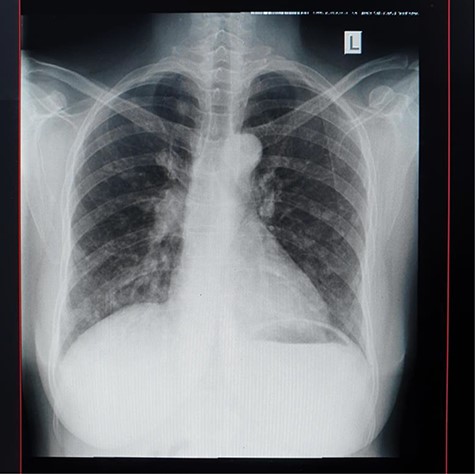

An abdominal ultrasound showed a mass in the posterior wall of the urinary bladder measuring 6 cm × 7 cm with areas of necrosis. There was left moderate ureter hydronephrosis. The right kidney and the rest visceral organs were normal. Chest X-ray revealed multiple macronodules all over the lung fields. Heart size, costophrenic and cardiophrenic angles were all normal (Fig. 6).

Urethrocystoscopy found to have extensive sand patch lesion in the urinary bladder with solitary solid tumor on the right side of the bladder wall extending from 3 to 5 o’clock. A transurethral resection of bladder tumor biopsy (TURBx) was done, and histological findings confirmed adenocarcinoma of the bladder with numerous calcified submucosal Schistosoma eggs (Fig. 7).

(A) Histopathology of urinary bladder with invasive adenocarcinoma, not otherwise specified (NOS), H&E ×10 magnification. (B) Schistosoma ova near or within the tumor, ×4 magnification.

The final diagnosis of metastatic adenocarcinoma of the urinary bladder was made and the patient was referred for palliative radiation therapy.